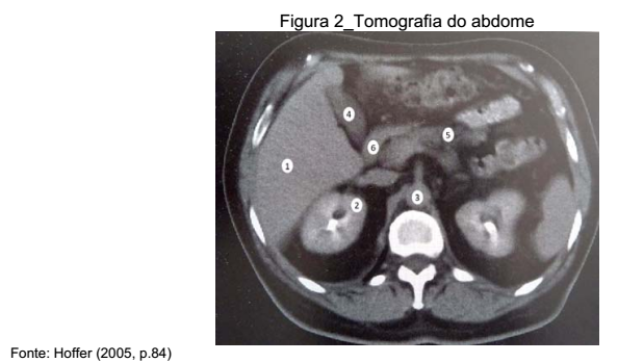

Q55887

A alternativa que contém, respectivamente, os pontos anatômicos correspondentes à sequência de 1 a 6 é

resolva Q55887 | Comente a Questão (coloque o Nº "Q55887") | » Apostila de Radiologia 2025